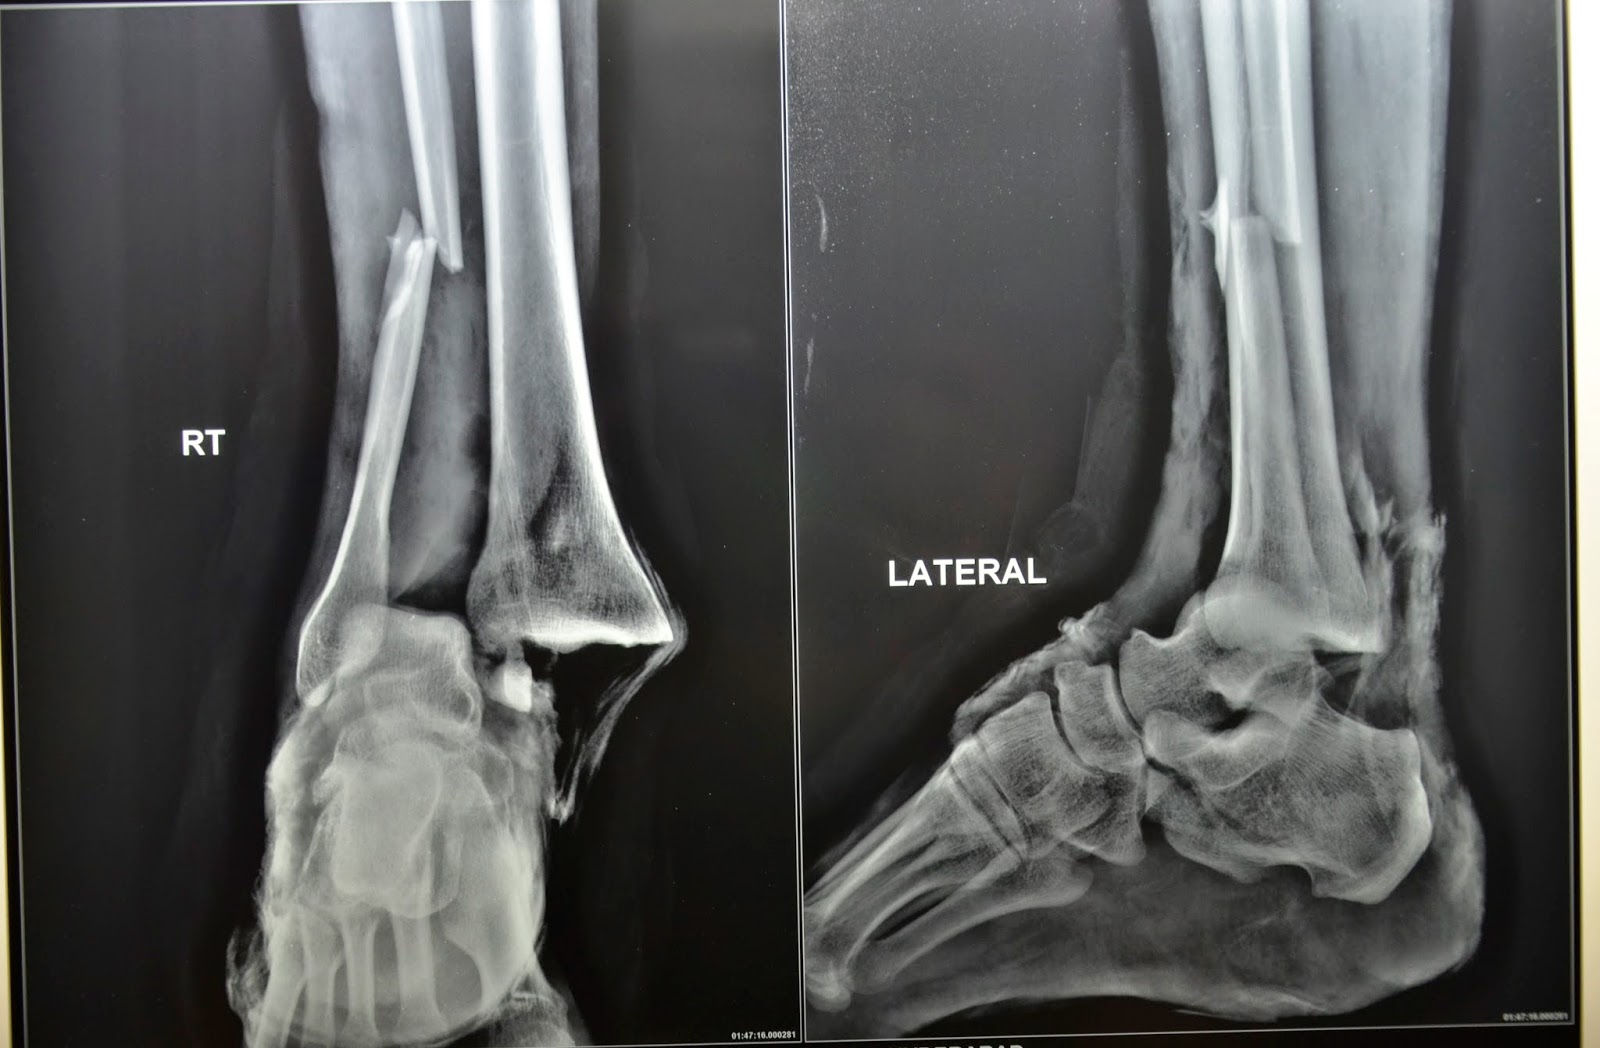

ANKLE FRACTURE BEFORE AND AFTER Ankle Fracture Cast Duration Ankle fractures are common injuries that could result from a trivial twisting injury in old frail patients up to high energy trauma in a. accepted 9 june 2021. “twisting” or rotating your ankle. Objectives to assess function, quality of life, resource use, and complications in adults. Ankle fractures can take a long time to heal. ankle fractures are. Ankle Fracture Cast Duration.

Xrays of Ankle Fractures Bone and Spine Ankle fracture, Ankle Ankle Fracture Cast Duration for a simple break in one bone that is stable, your doctor may recommend using a walking boot or cast for about six weeks to protect. Ankle fractures are common injuries that could result from a trivial twisting injury in old frail patients up to high energy trauma in a. Ankle fractures can take a long time to heal.. Ankle Fracture Cast Duration.